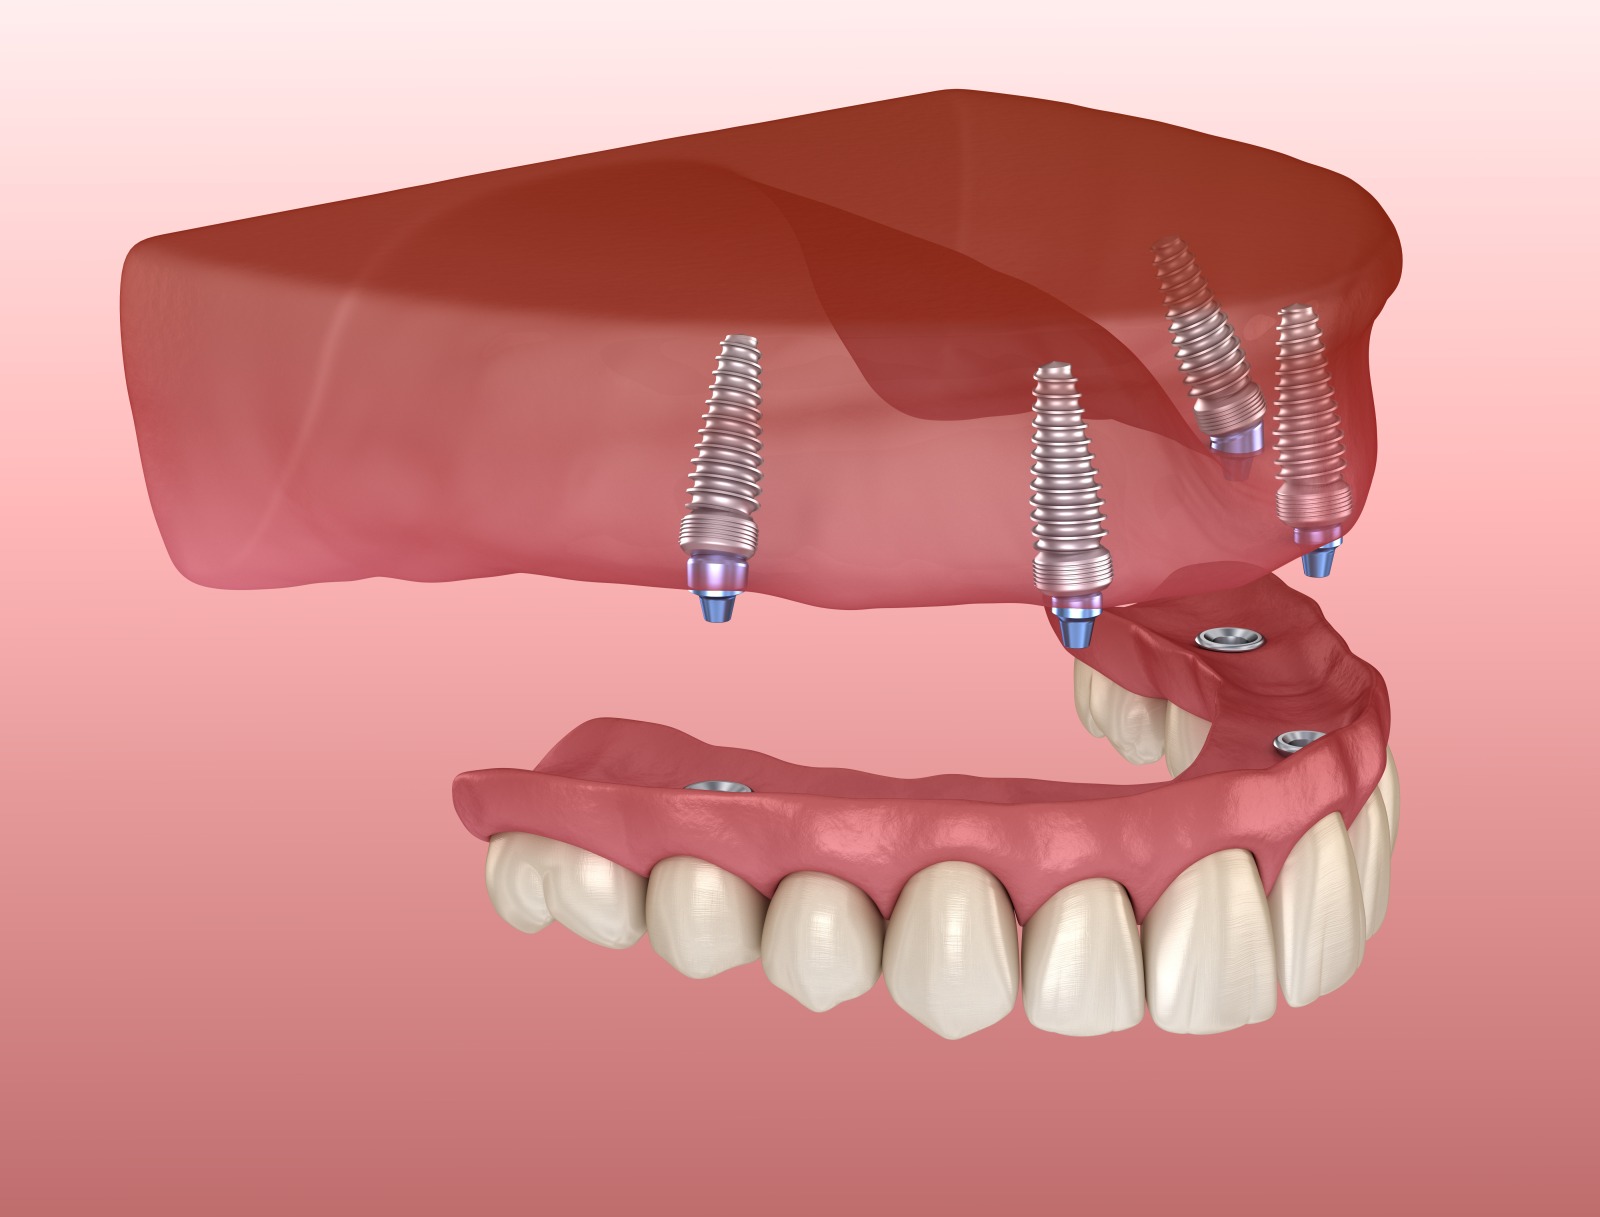

短期で機能的な歯を手に入れる治療法

当院では、例えばインプラント治療であれば、抜歯したその日から噛める歯が入る「抜歯即時荷重インプラント」、さらに1回の手術ですべての歯がそろう「オールオン4」。入れ歯治療であれば、初診から最短で翌日には仮の入れ歯ができる「スピードデンチャー」など、高い技術を要する治療が可能です。

どれも機能性と審美性を兼ね備えつつ、治療期間の短縮にもつながります。